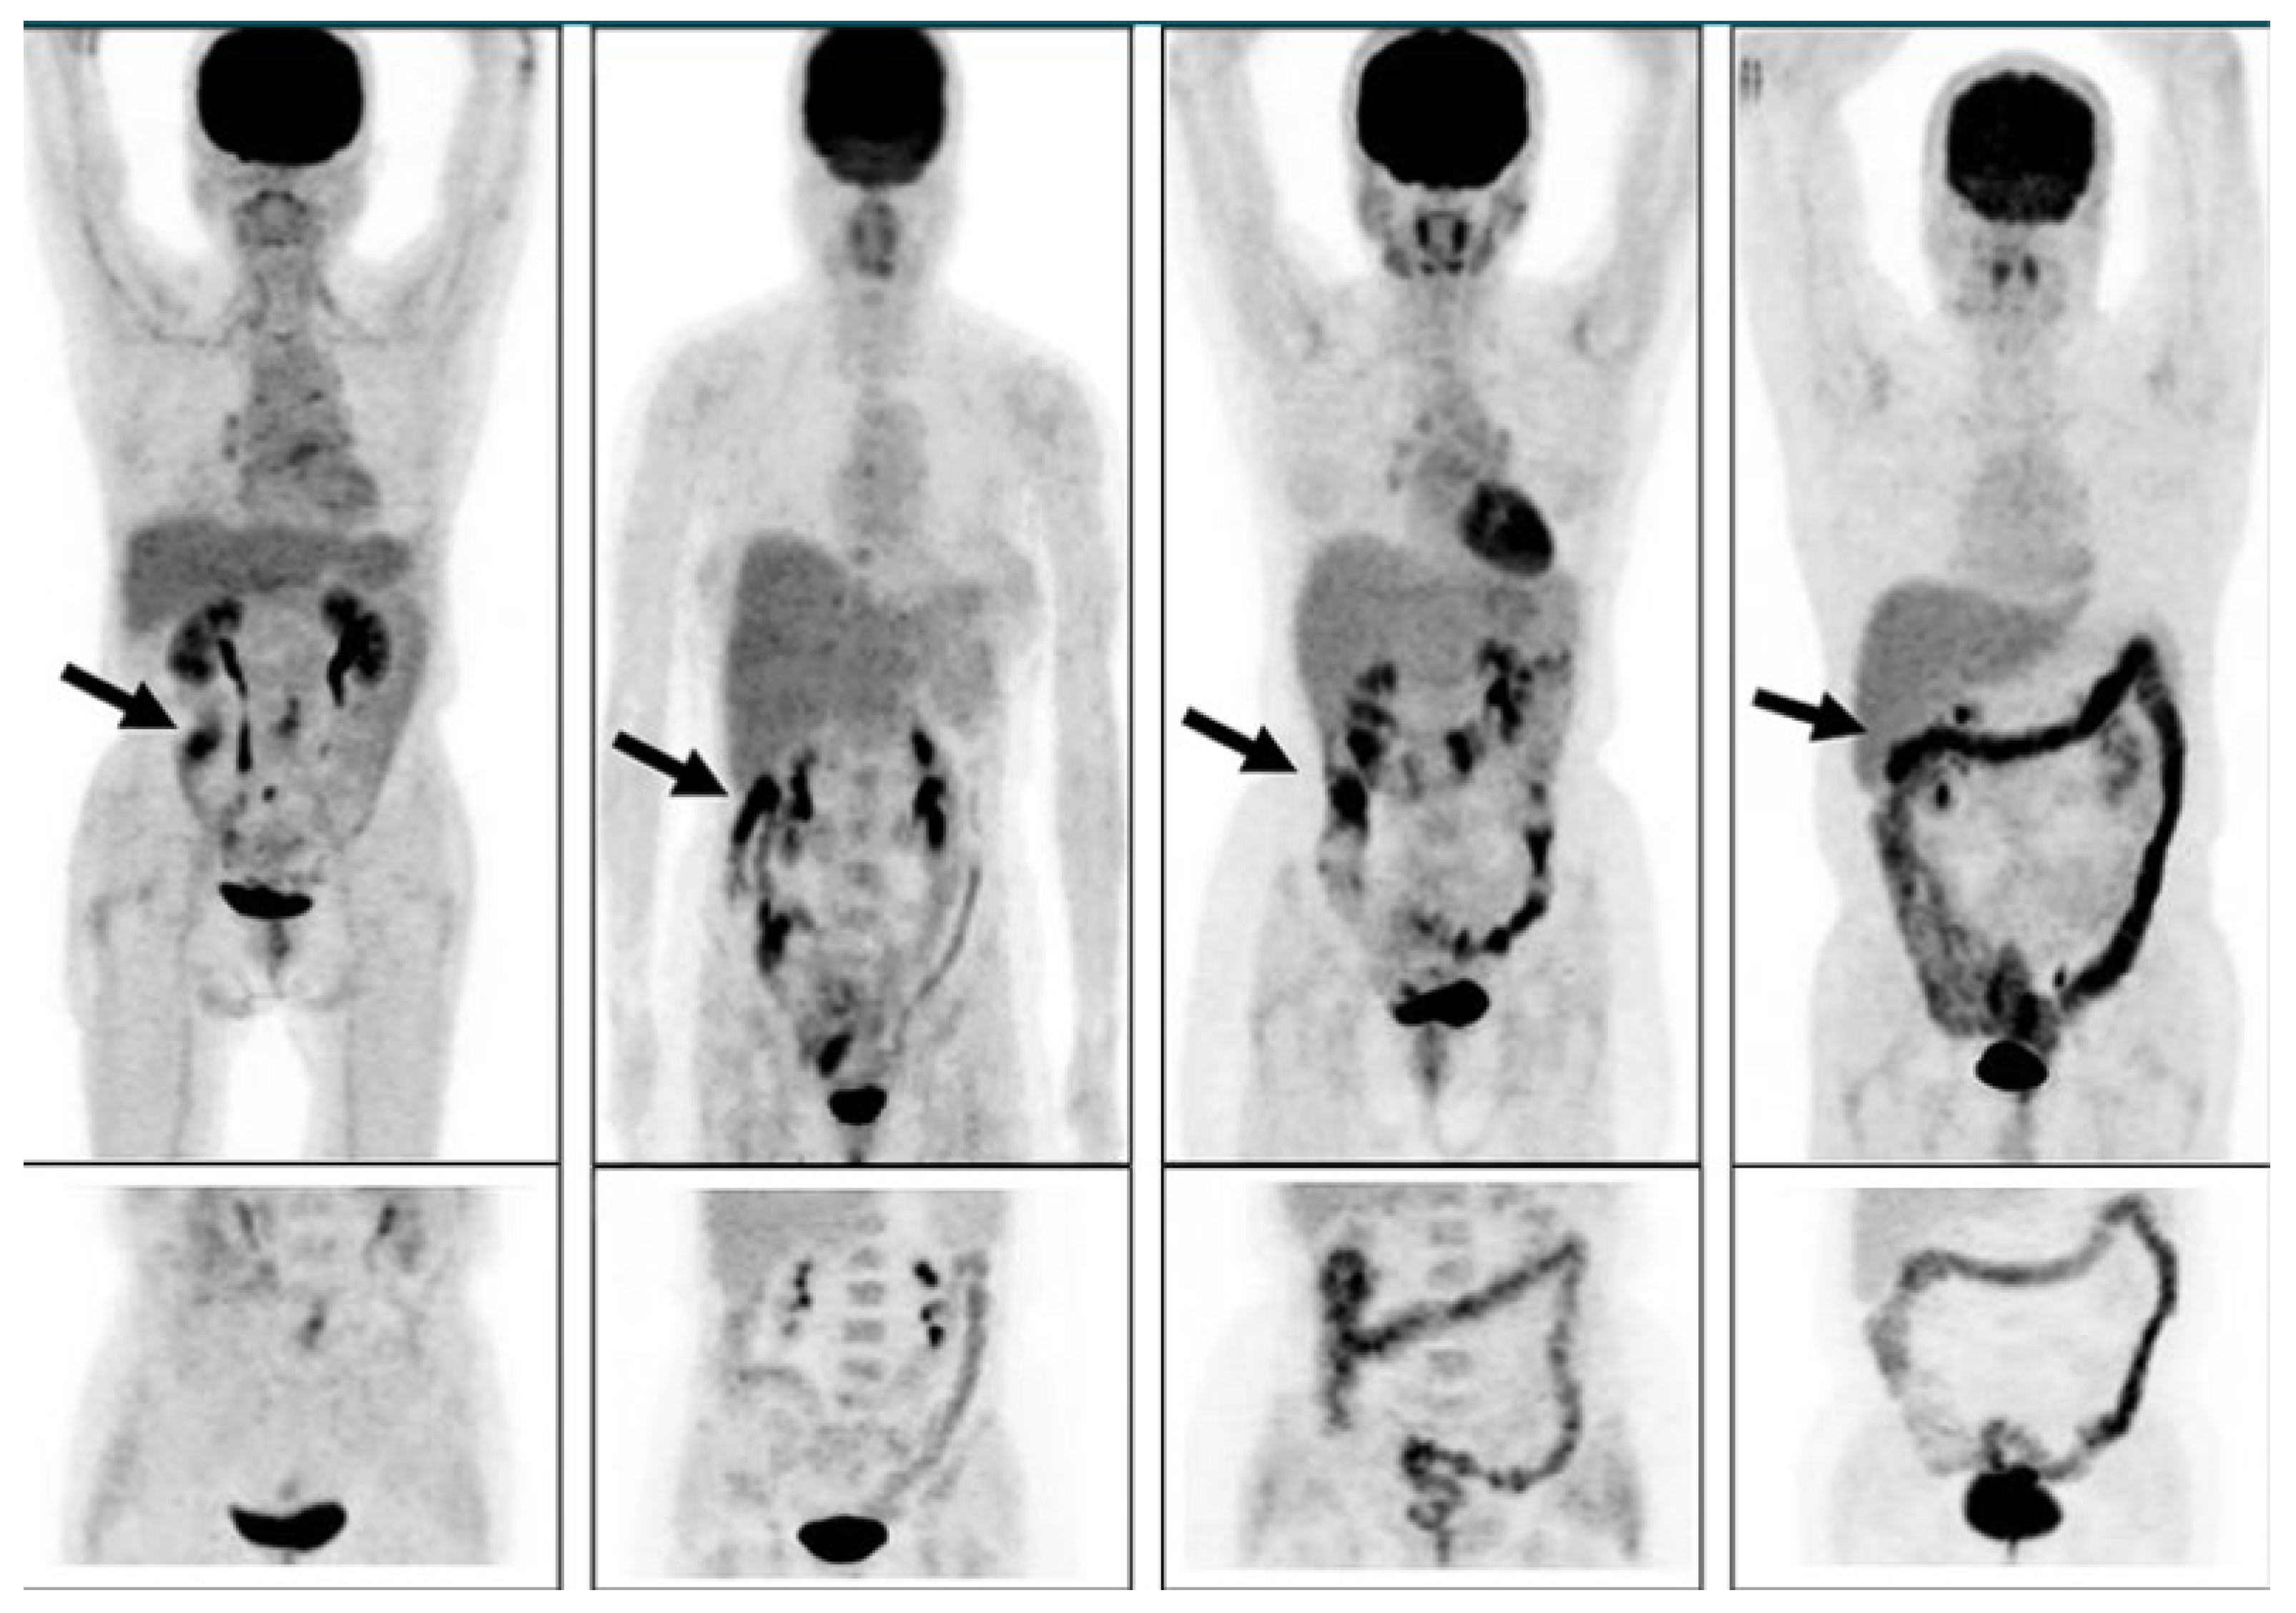

Accumulation of F18-FDG in the large intestine (Figure 4) has been found also in persons who regularly use laxatives [175,176]. SUVmax can even reach levels that simulate those of colorectal neoplasms (Figure 5) in patients with chronic constipation [177].

Figure 4.

PET pictures of early scans (upper row) and of late FDG scans (lower row) after oral administration of laxatives. The arrows in the upper row of PET scans show the different patterns of accumulation of the tracers in the large intestine. From Chen Y-K et al. ([176], with permission).

Figure 5.

Accumulation of radioactivity after intravenous administration in the coecum and ascending colon (upper panel, long arrow) of a patient using anthraquinone laxatives, as demonstrated by the presence of melanosis coli at colonoscopy performed to exclude colon cancer (lower panel, short arrow). From Katsumata R [177].